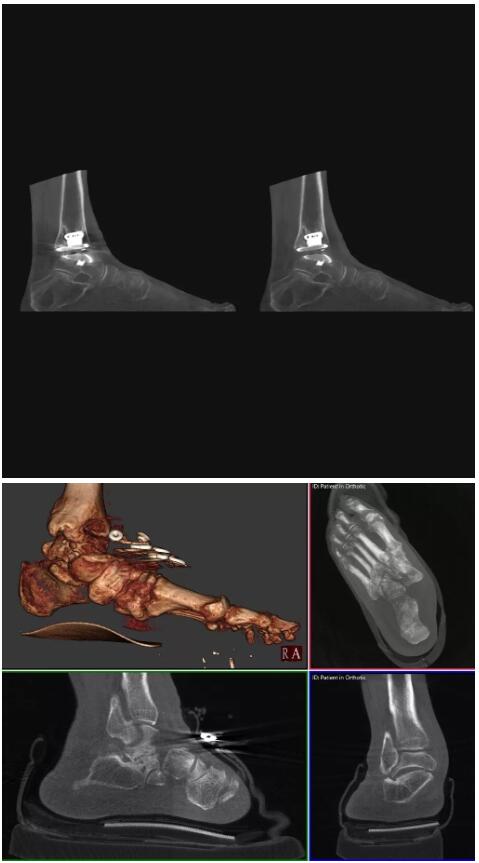

比如上面這款專用于足部和踝部掃查的CT成像系統(tǒng),患者在進(jìn)行CT掃查時(shí)只需要站在上面即可,雙腳站或者單腳站都可以,當(dāng)然,如果患者不是那么方便站著做完CT掃查,也可坐在上面。

這款CT掃查系統(tǒng)自帶屏蔽裝置,它的體積非常小,僅需要極小的空間即可,并不像常規(guī)CT那樣需要一間單獨(dú)的檢查室。此外,這種CT掃查的速度非???,僅需30秒左右可以完成檢查,輻射劑量相對常規(guī)的CT要少許多,尤其適合醫(yī)院的骨科使用。

而患者站著做足部或者踝部做CT檢查還有個(gè)好處是,可以檢查患者在負(fù)重的情況下,骨關(guān)節(jié)的真實(shí)情況,而躺著做CT掃查時(shí)未必能看出來。負(fù)重CT掃查特別是對于受傷的運(yùn)動員或者舞蹈員來說意義更大,能夠更準(zhǔn)確地評估傷情,幫助他們盡早復(fù)原。

以下是這些“特立獨(dú)行”的CT所拍出來的圖像: